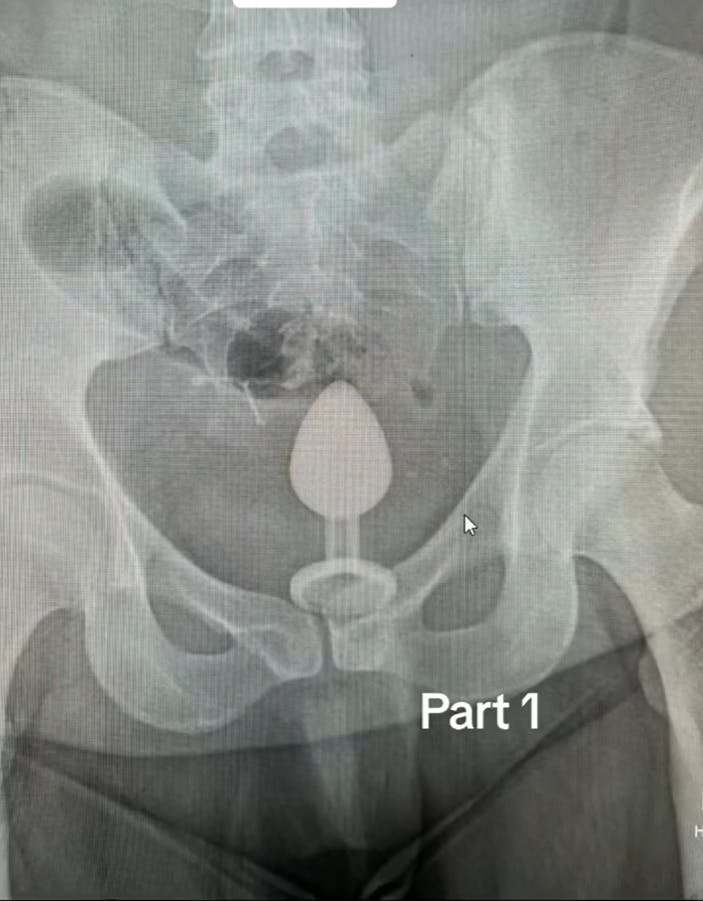

Efter en lidt væmmelig, ti-minutters tur til skadestuen i en taxa fik Gigi Chapman taget et røntgenbillede for at se, hvor langt oppe legetøjet egentlig var.

Den skjuler sig ikke særlig godt på røntgenbilledet.